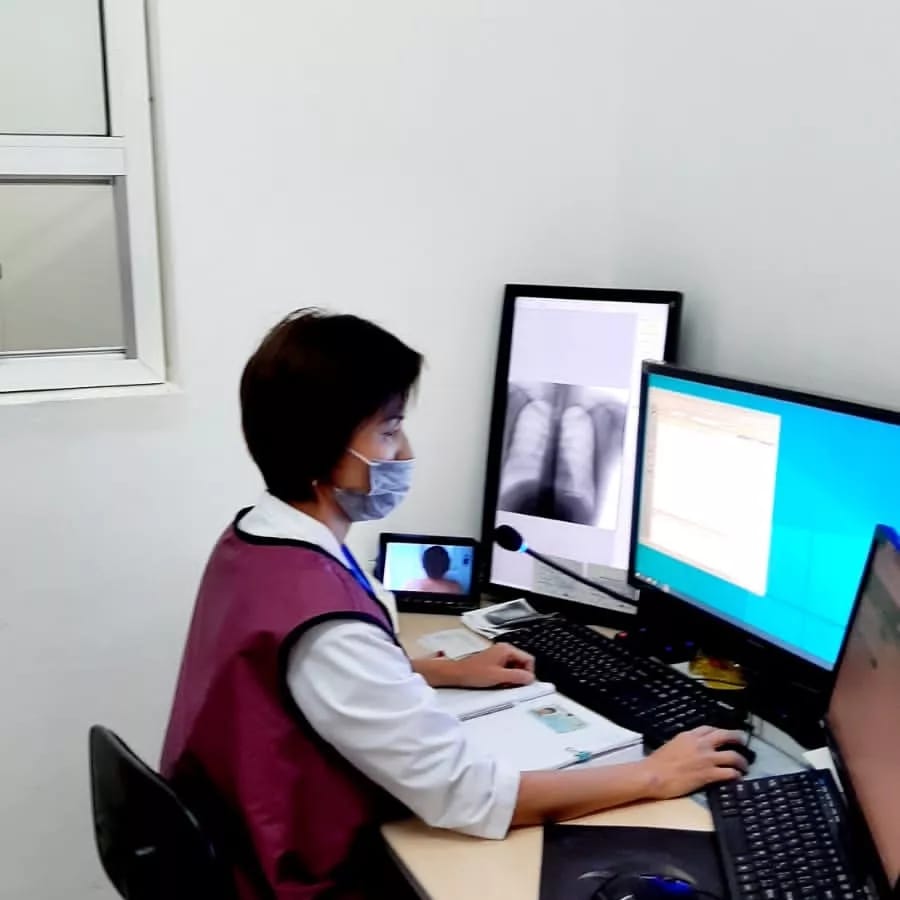

Функции и возможности Proscan Softportal

Раздел: Фотозарисовки